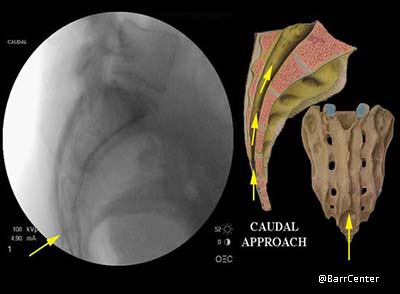

Caudal: the injection is placed through a small opening (sacral canal) just above the tailbone.

In the caudal approach for an epidural steroid injection, the needle is passed through a small opening (sacral canal) just above the tailbone.